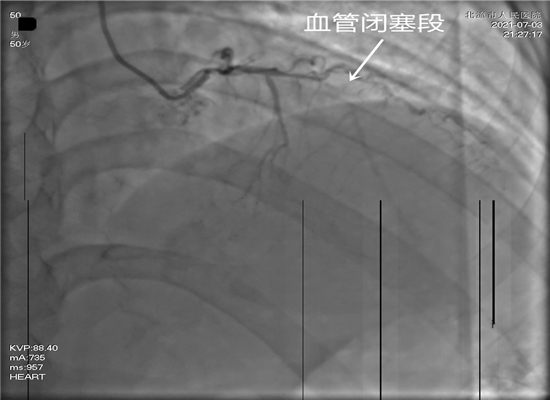

放支架前,显示血管闭塞